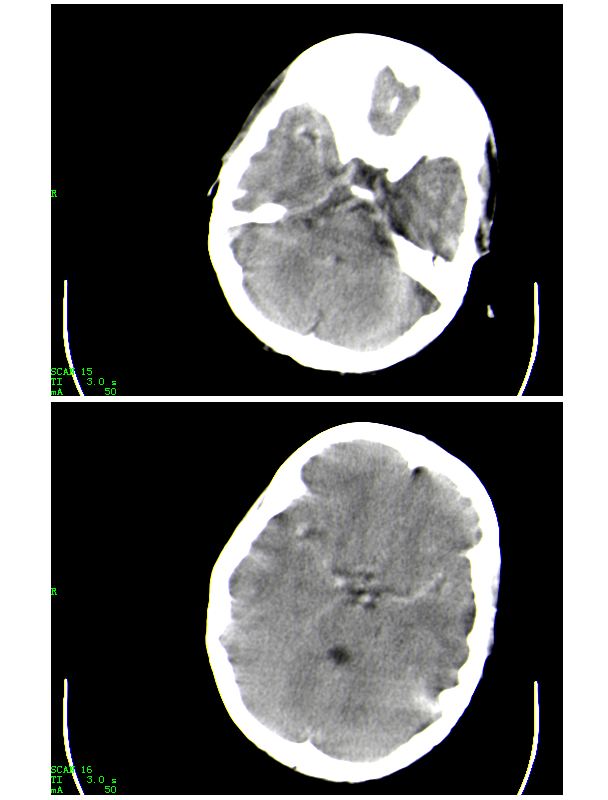

下面是第二天的复查和受伤后第五天的复查,左侧硬膜下血肿有所吸收,脑内条状高密度无改变

第五天的复查片

导致的原因楼上的战友已经讲的非常好了,再加深点印象

人体血液中影响ct值的主要成分是有形成分红细胞和血浆中的蛋白质,尤其室含铁的hb,其占血液中蛋白质总量的大部分,亦是引起血液ct密度变化的主要因素。hb含量与ct值间具有相关性,noman等的研究表明hb含量每改变10g/l,相应ct值变化为1.86hu。

本病主要应与蛛网膜下腔出血相鉴别,鉴别要点:

(1)高密度血管网络旁仍见清晰、正常低密度脑脊液影;

(2)临床没有急性颅内出血的症状何体征。